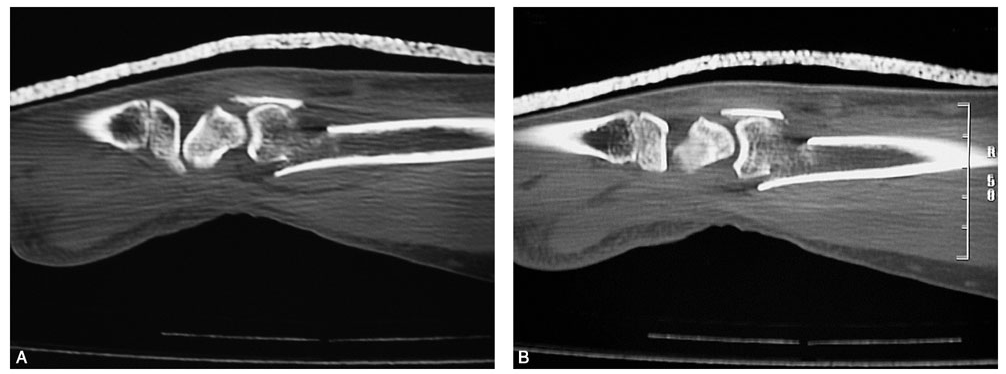

术前拍腕关节正、侧位X线片,腕关节冠状位、矢状位和水平位CT(图2-2)。此患者骨缺损和无法闭合复位的骨片均在背侧,宜采用背侧入路,复位,植骨,固定。取患肢前臂远端桡背侧纵切口(图2-3),从伸拇长肌腱和桡侧伸腕长、短肌之间进入,注意保护血管神经和肌腱,显露清理折端骨缺损区域和背侧移位的骨片(图2-4),复位,植骨,外固定架超关节固定(图2-5、图2-6)。术中透视骨折复位固定满意(图2-7),术后拍X线片证实(图2-8)。此手术的优点在于避免了局部存在内固定物的刺激,避免二期切开取出固定物所致的再次损伤。

图2-2 骨缺损和无法闭合复位的骨片均在背侧

图2-4 显露桡骨远端背侧骨缺损区和移位的骨片

图2-6 显示植骨和骨片复位